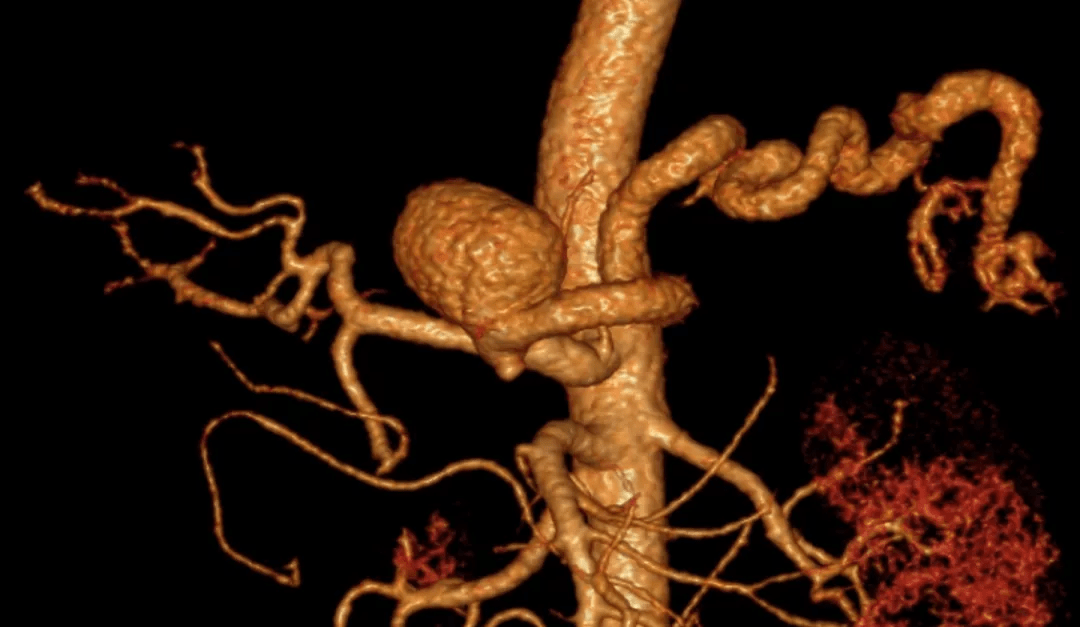

腹腔干动脉瘤

进食后腹痛数月"来院检查,腹部ct发现"腹主动脉瘤,腹腔干动脉瘤